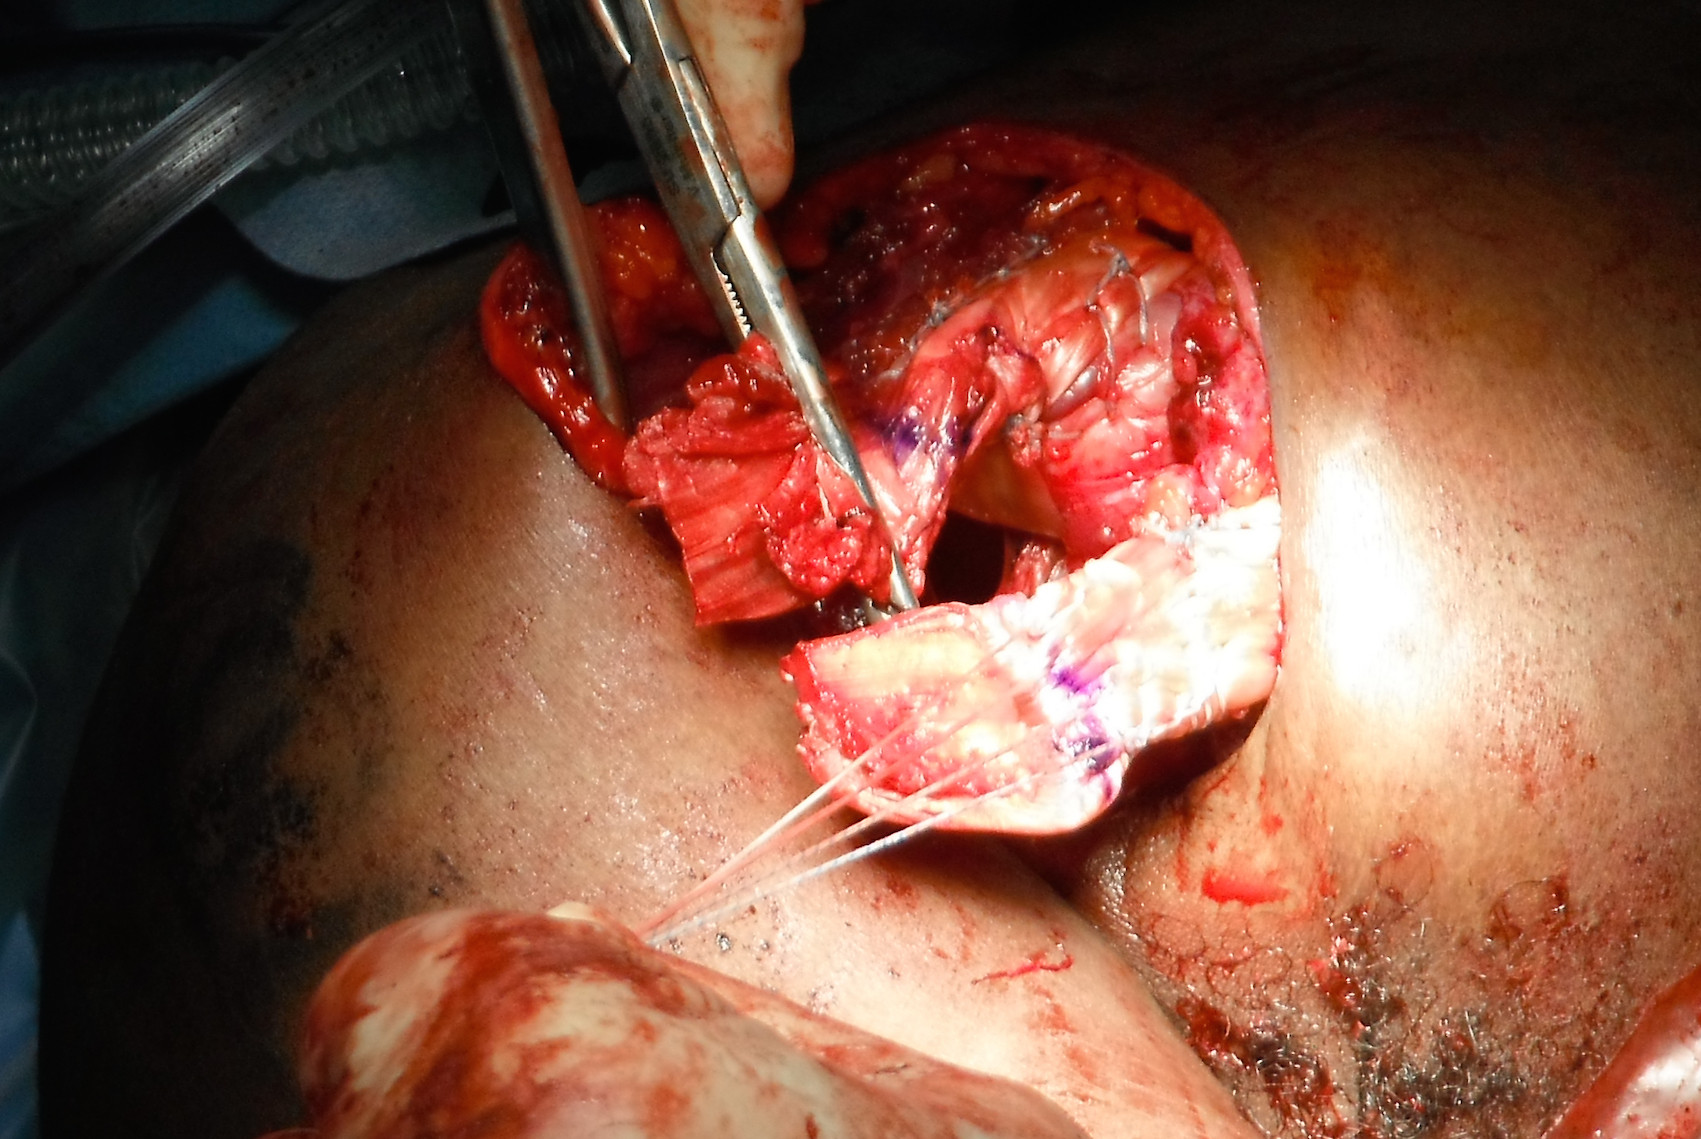

Pec majorpec

Acute musculotendinous pectoralis major rupture

Pec majorPec major

Allograft reconstruction: achilles tendon sutured anchored to humerus, and pul ve taft through muscle belly